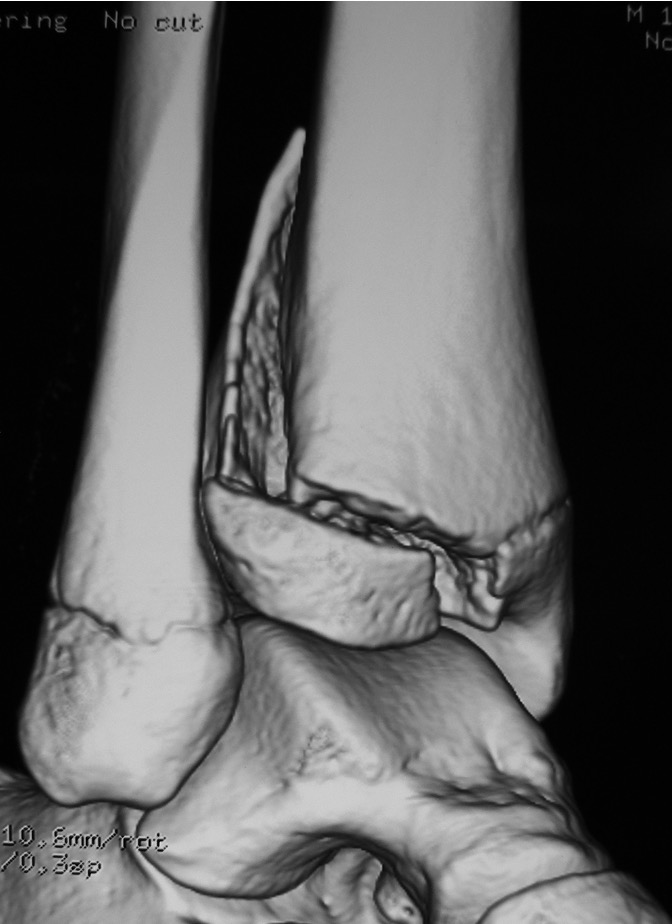

Triplanar Fracture

Definition

Fracture in coronal, sagittal and transverse planes

- crosses epiphysis

- passes through growth plate

- extends into metaphysis

Transitional fracture

- occurs near skeletal maturity

- age 12 - 15

- medial physis is closed

- lateral physis remains open

Xray

AP xray: Salter-Harris type III / Tillaux

Lateral xray: Salter-Harris Type II

CT

Coronal images: Salter-Harris type III

Sagittal images: Salter-Harris type II

Axial images: 3 point star